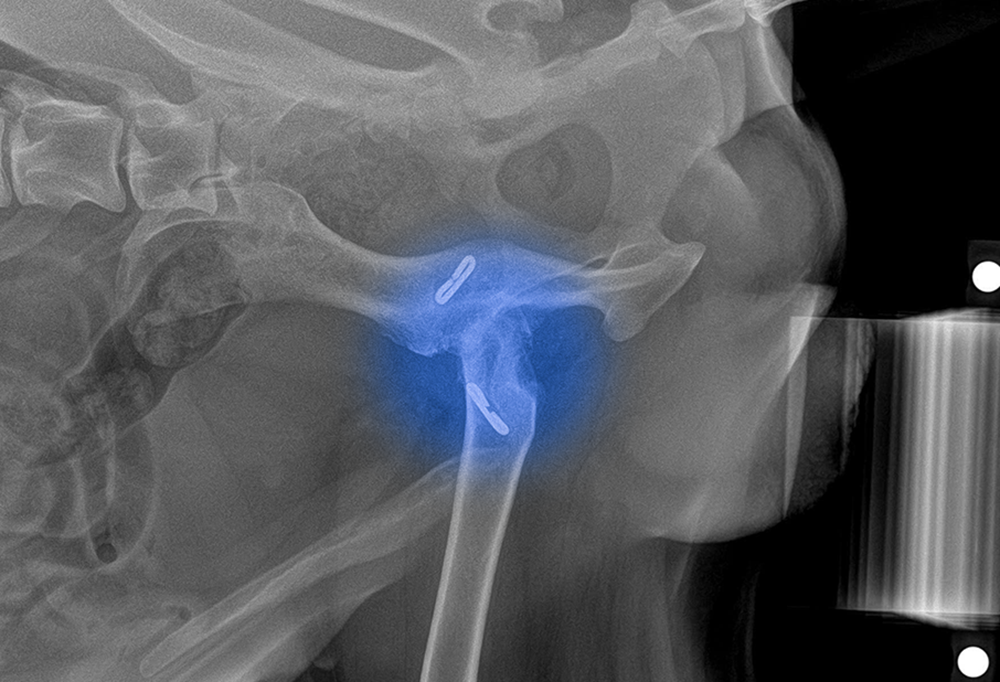

Qua thăm khám và hình ảnh X-quang, các bác sĩ phát hiện khớp háng của Sky đã bắt đầu tái tổn thương, dẫn đến thoái hóa ổ cối – vị trí tiếp giáp quan trọng giữa chỏm xương đùi và xương chậu.

Kết quả chiếu chụp cho thấy những hư hại nặng nề:

- Ổ cối đã bị xơ hóa nghiêm trọng.

- Cấu trúc khớp bị biến dạng.

- Mất kết nối hoàn toàn giữa chỏm xương đùi và xương chậu.

Chính điều này khiến khớp háng mất đi sự ổn định, gây đau đớn kéo dài và làm suy giảm nghiêm trọng khả năng vận động của Sky.